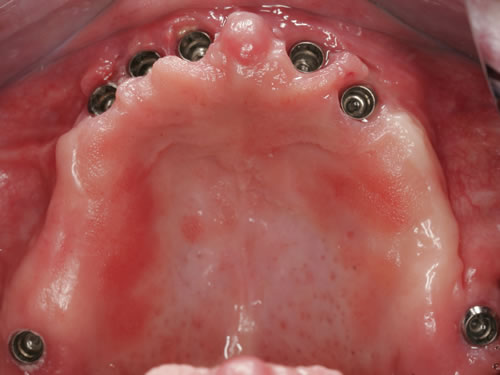

Bei dieser Ausgangssituation kann nicht in allen Fällen durch den Einsatz von Implantaten geholfen werden. Im Oberkiefer ist die Knochensituation meist ungünstiger als im Unterkiefer. Wenn allerdings ausreichend Knochen vorhanden ist oder geschaffen werden kann, lässt sich durch die Einpflanzung einiger Pfeiler die Prothese erheblich verkleinern und in Einzelfällen sogar eine Brücke anfertigen. Der Zahnersatz kann dann ohne jeden Würgereiz getragen werden (Abb. 3.15 bis 3.18).

Abb. 3.15: Zahnloser Oberkiefer mit sieben Implantaten versorgt.

Abb. 3.16: Eingeschraubte Unterkonstruktion zur Befestigung des zahntragenden Anteils.

Abb. 3.17: Eingesetzte herausnehmbare, gaumenfreie Brücke.

Für den Oberkiefer ist eine CT-Untersuchung notwendig, die ebenfalls mit einer Schablone durchgeführt wird. Auswertung, Planung und Implantations-Simulationen ergeben, dass sechs Implantate im vorderen Kieferabschnitt verankert werden können. Auch die Qualität des Knochens lässt eine Einpflanzung ohne weitere Maßnahmen zu. Diese Behandlung soll nach der Versorgung des Unterkiefers erfolgen.